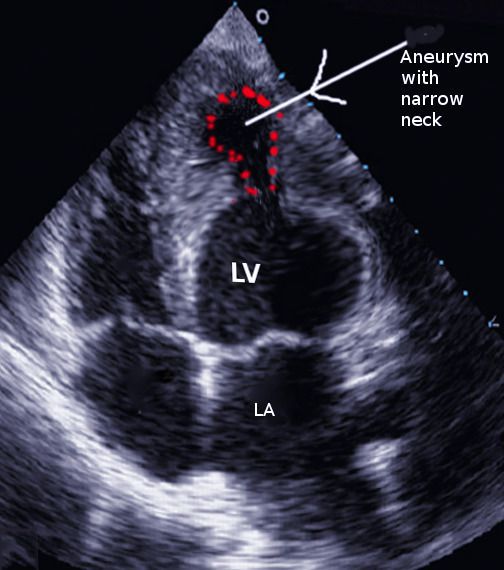

Ventricular Aneurysm in Post-Myocardial Patients

One of the complications of Myocardial Infarction in ventricular aneurysm. It arises secondary to ventricular wall weakness. Image via: https://www.ncbi.nlm.nih.gov/books/NBK551519/figure/article-24162.image.f2/